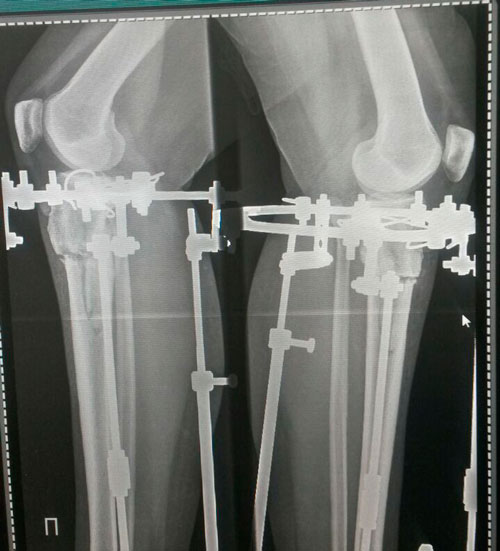

Дата операции 15.01.2018г.

Дата снятия аппаратов 23.04.2018г.

Срок лечения 97 дней.